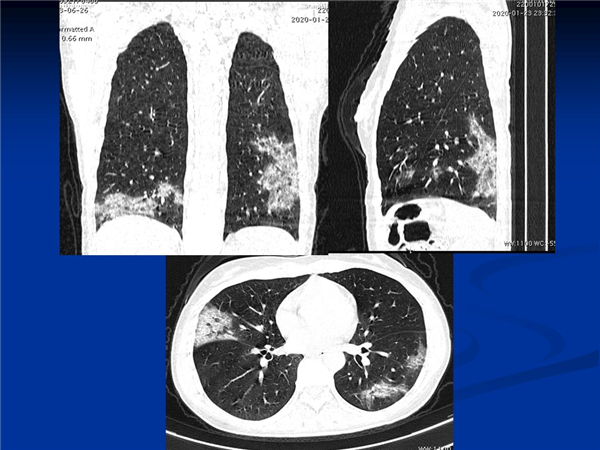

【病例分享】新型冠狀病毒感染肺部CT影像4例(常德市第一人民醫(yī)院)